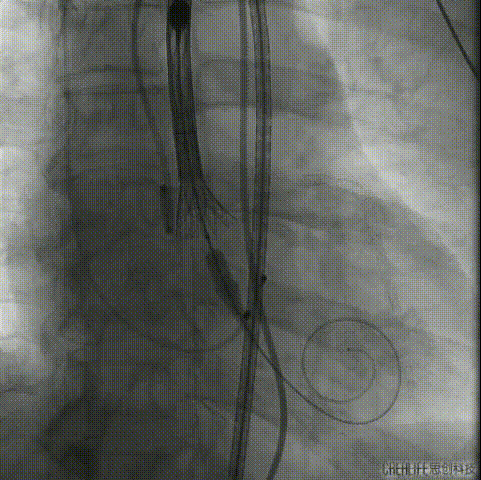

术中操作

根部造影

定位

第一次释放

第一次释放定位过高

回收

第二次释放

释放至可回收极限